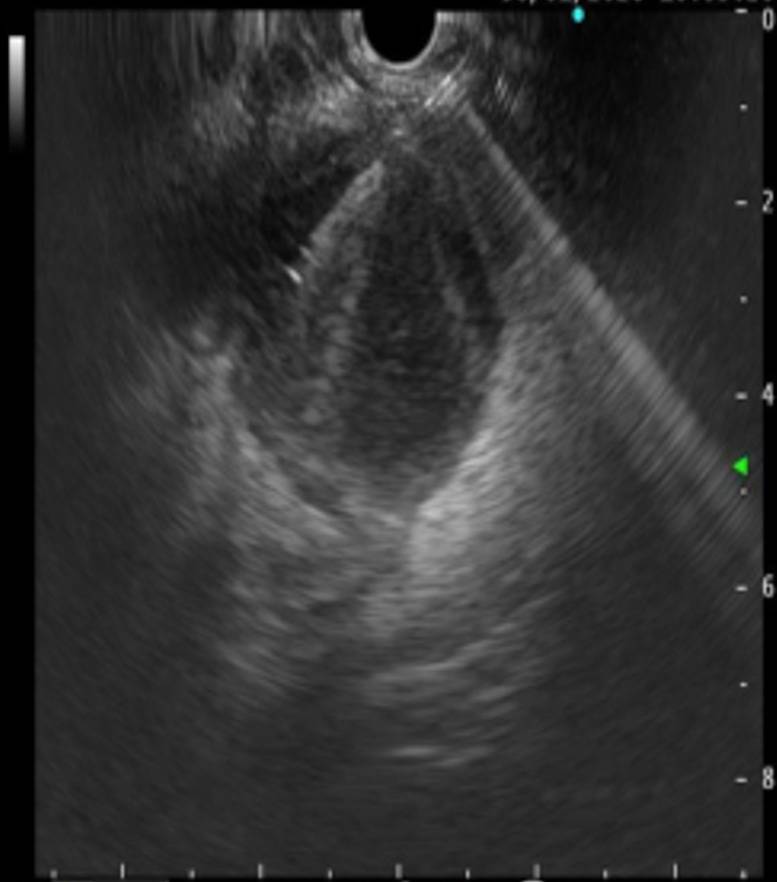

超声内镜引导下脓肿穿刺

术前CT显示直肠前方一直径5cm圆形脓肿